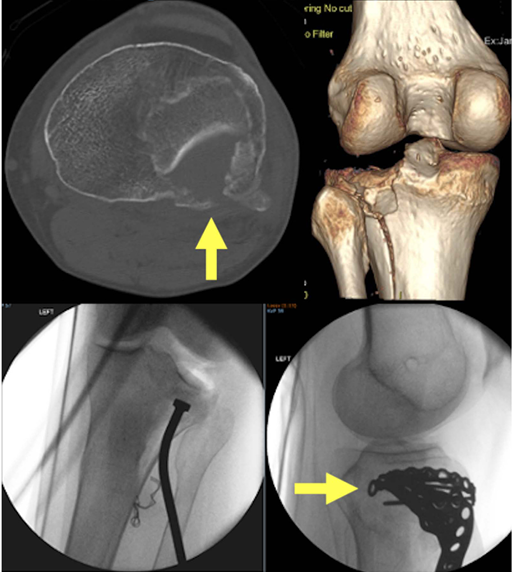

本入路的局限: 该入路的一个局限在于难以直接操作后外侧骨折块进行复位。然而,可以放置点式复位钳,并通过观察皮质骨折缘来评估复位质量。对于轻度的斜坡状关节面塌陷,可在胫骨前外侧干骺端开一皮质骨窗,由此通道进行关节面抬升。如下图:

图示说明:运用扩展前外侧入路处理一例Kfuri-Schatzker type II A + P型骨折。通过一个前外侧皮质骨窗(骨凿插入处),为抬升后外侧象限的塌陷关节面提供了通路(箭头所示)。水平钢板(箭头所示)实现了对后外侧象限的筏式固定,并包容了后外侧和前外侧的关节缘。